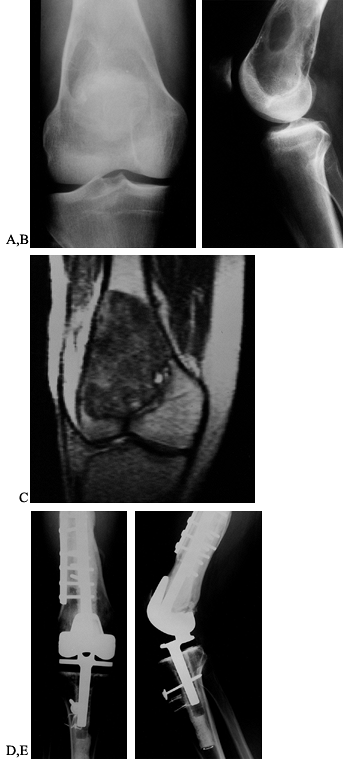

![]() |

Figure 126.4. A: Anteroposterior (AP) radiograph of an 8-year-old girl with osteosarcoma of distal femur. B: Lateral radiograph of osteosarcoma. Note the bone destruction and periosteal reaction. C:

AP radiograph after resection of the distal femur. The knee is reconstructed with an expandable custom prosthesis. The articulation is a constrained condylar device. The expansion mechanism is at the top of the prosthesis. D: Lateral radiograph of an expandable knee prosthesis. |